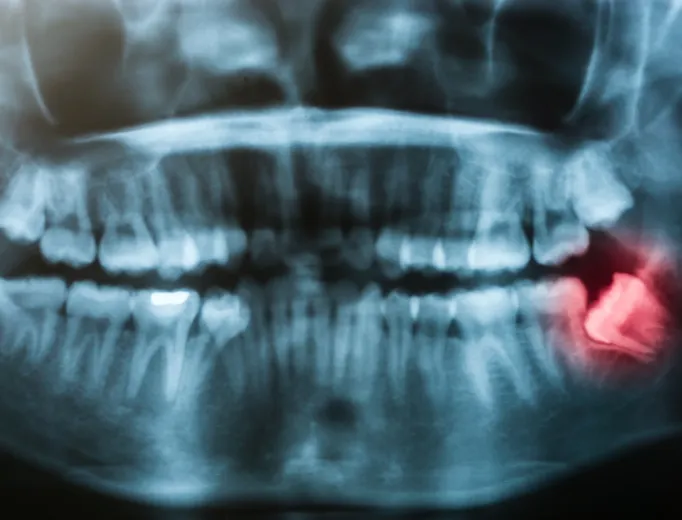

Not all wisdom teeth require extraction, but if they pose a risk to oral health, Dr. Krista Farr, Dr. Jessica Bains and Dr. Eric Mack may recommend their removal. Some patients experience pain, swelling or difficulty opening their mouths, which can indicate infection or impaction. Even if wisdom teeth are not currently causing discomfort, they may still contribute to issues that develop over time. Our dentists will assess your teeth through a clinical exam and digital imaging to determine whether removal is necessary.What to Expect During the Procedure

Wisdom teeth removal is a common oral surgery procedure performed under local anesthesia, sedation or general anesthesia, depending on the complexity of the case. During the procedure, our dentists or trusted oral surgeon will carefully remove the teeth while minimizing impact to surrounding tissue. If the teeth are impacted, small incisions may be made in the gums and the teeth may be sectioned for easier removal.Recovery & Aftercare